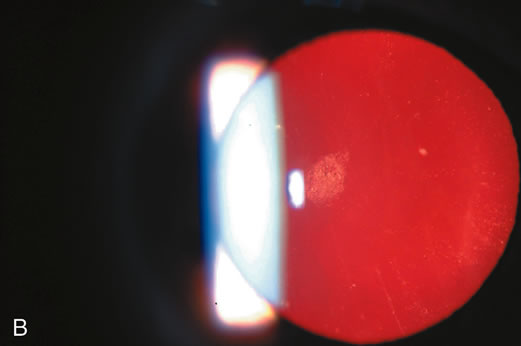

Fig. 1. Cortical cataract using (A) direct illumination (B) retroillumination. Cortical cataracts usually start in the lens periphery and encroach into the visual axis (and interfere with central vision) only in later stages.

Retroillumination uses the light reflected from the fundus to highlight opacities. This is very useful in examining cortical and posterior subcapsular cataracts (Figs. 1, 3, 7, and 8). However, some cortical water clefts and early posterior subcapsular opacities may not be easily seen with retroillumination if they are not dense enough to cast shadows or only refract the retroilluminate light; these can be best seen with the broad beam. Using retroillumination on nuclear cataracts does not give much information because these usually do not cast shadows. However, as seen in Figure 2B, a change in the refractive index can be seen toward the center. Usually, the outline of the nuclear cataract can be seen as a result of a “magnifying lens” artifact. This is also easily observed during direct and indirect ophthalmoscopy. Several retroillumination cameras (modified slit lamps with the slit beam fixed for retroillumination and depolarizers built in to remove corneal reflex from the image) have been developed and are being used for documenting cortical and posterior subcapsular cataracts.49, 50

Retroillumination cameras49,50 obtain images of cortical and posterior subcapsular cataracts as shown in Figures 1B, 7, and 8. These are useful for both cross-sectional and longitudinal studies. Various manual or automated methods have been developed or are being developed for the analysis of these images to determine the size of opacities. Usually, an artificial mask with a chosen diameter is used to standardize the area of interest in the image, and either a percent area or area in square millimeters is determined. Because of the variability of the background light (the images are shadows of the cataracts using light that is backlighted from the retina or optic nerve), densitometry is unreliable. Among the methods used include computer planimetry, counting boxes, manual and automated edge detection, and automated area analysis. This method is also being used to study IOL decentration and posterior capsular opacification after cataract surgery. Examples of this type of device are the Nidek EAS 1000 retroillumination unit (Nidek, Pasadena, CA), Oxford retroillumination camera (Marcher Ltd., Hereford, UK), and Topcon CTR (Topcon Medical Systems, Paramus, NJ).